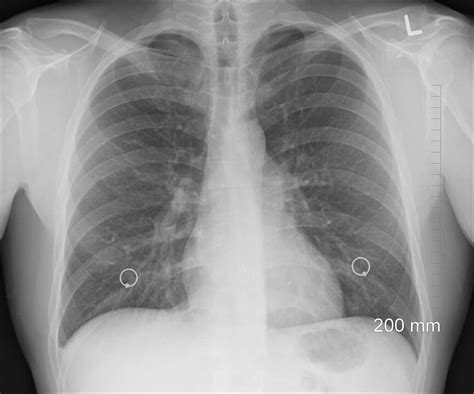

Zápal pľúc je vážne ochorenie, ktoré si vyžaduje okamžitú lekársku starostlivosť a dôslednú liečbu. V jednom z prípadov sa rodičia starali o dvojičky vo veku 3 rokov, ktoré mali diagnostikovaný zápal pľúc. Jeden z chlapcov bol v horšom stave a minulý víkend bol hospitalizovaný. Po podaní antibiotík teploty ustúpili a v stredu bol prepustený domov. Odvtedy boli doma a neboli vonku. Hoci boli bez horúčky už týždeň a užívali antibiotiká, rodičia si neboli istí, či môžu deti vziať na dvor na hodinku denne. Pľúcna lekárka im odporučila nikam neplánovane neprechádzať, zatiaľ čo obvodná lekárka súhlasila s krátkym pobytom na dvore.